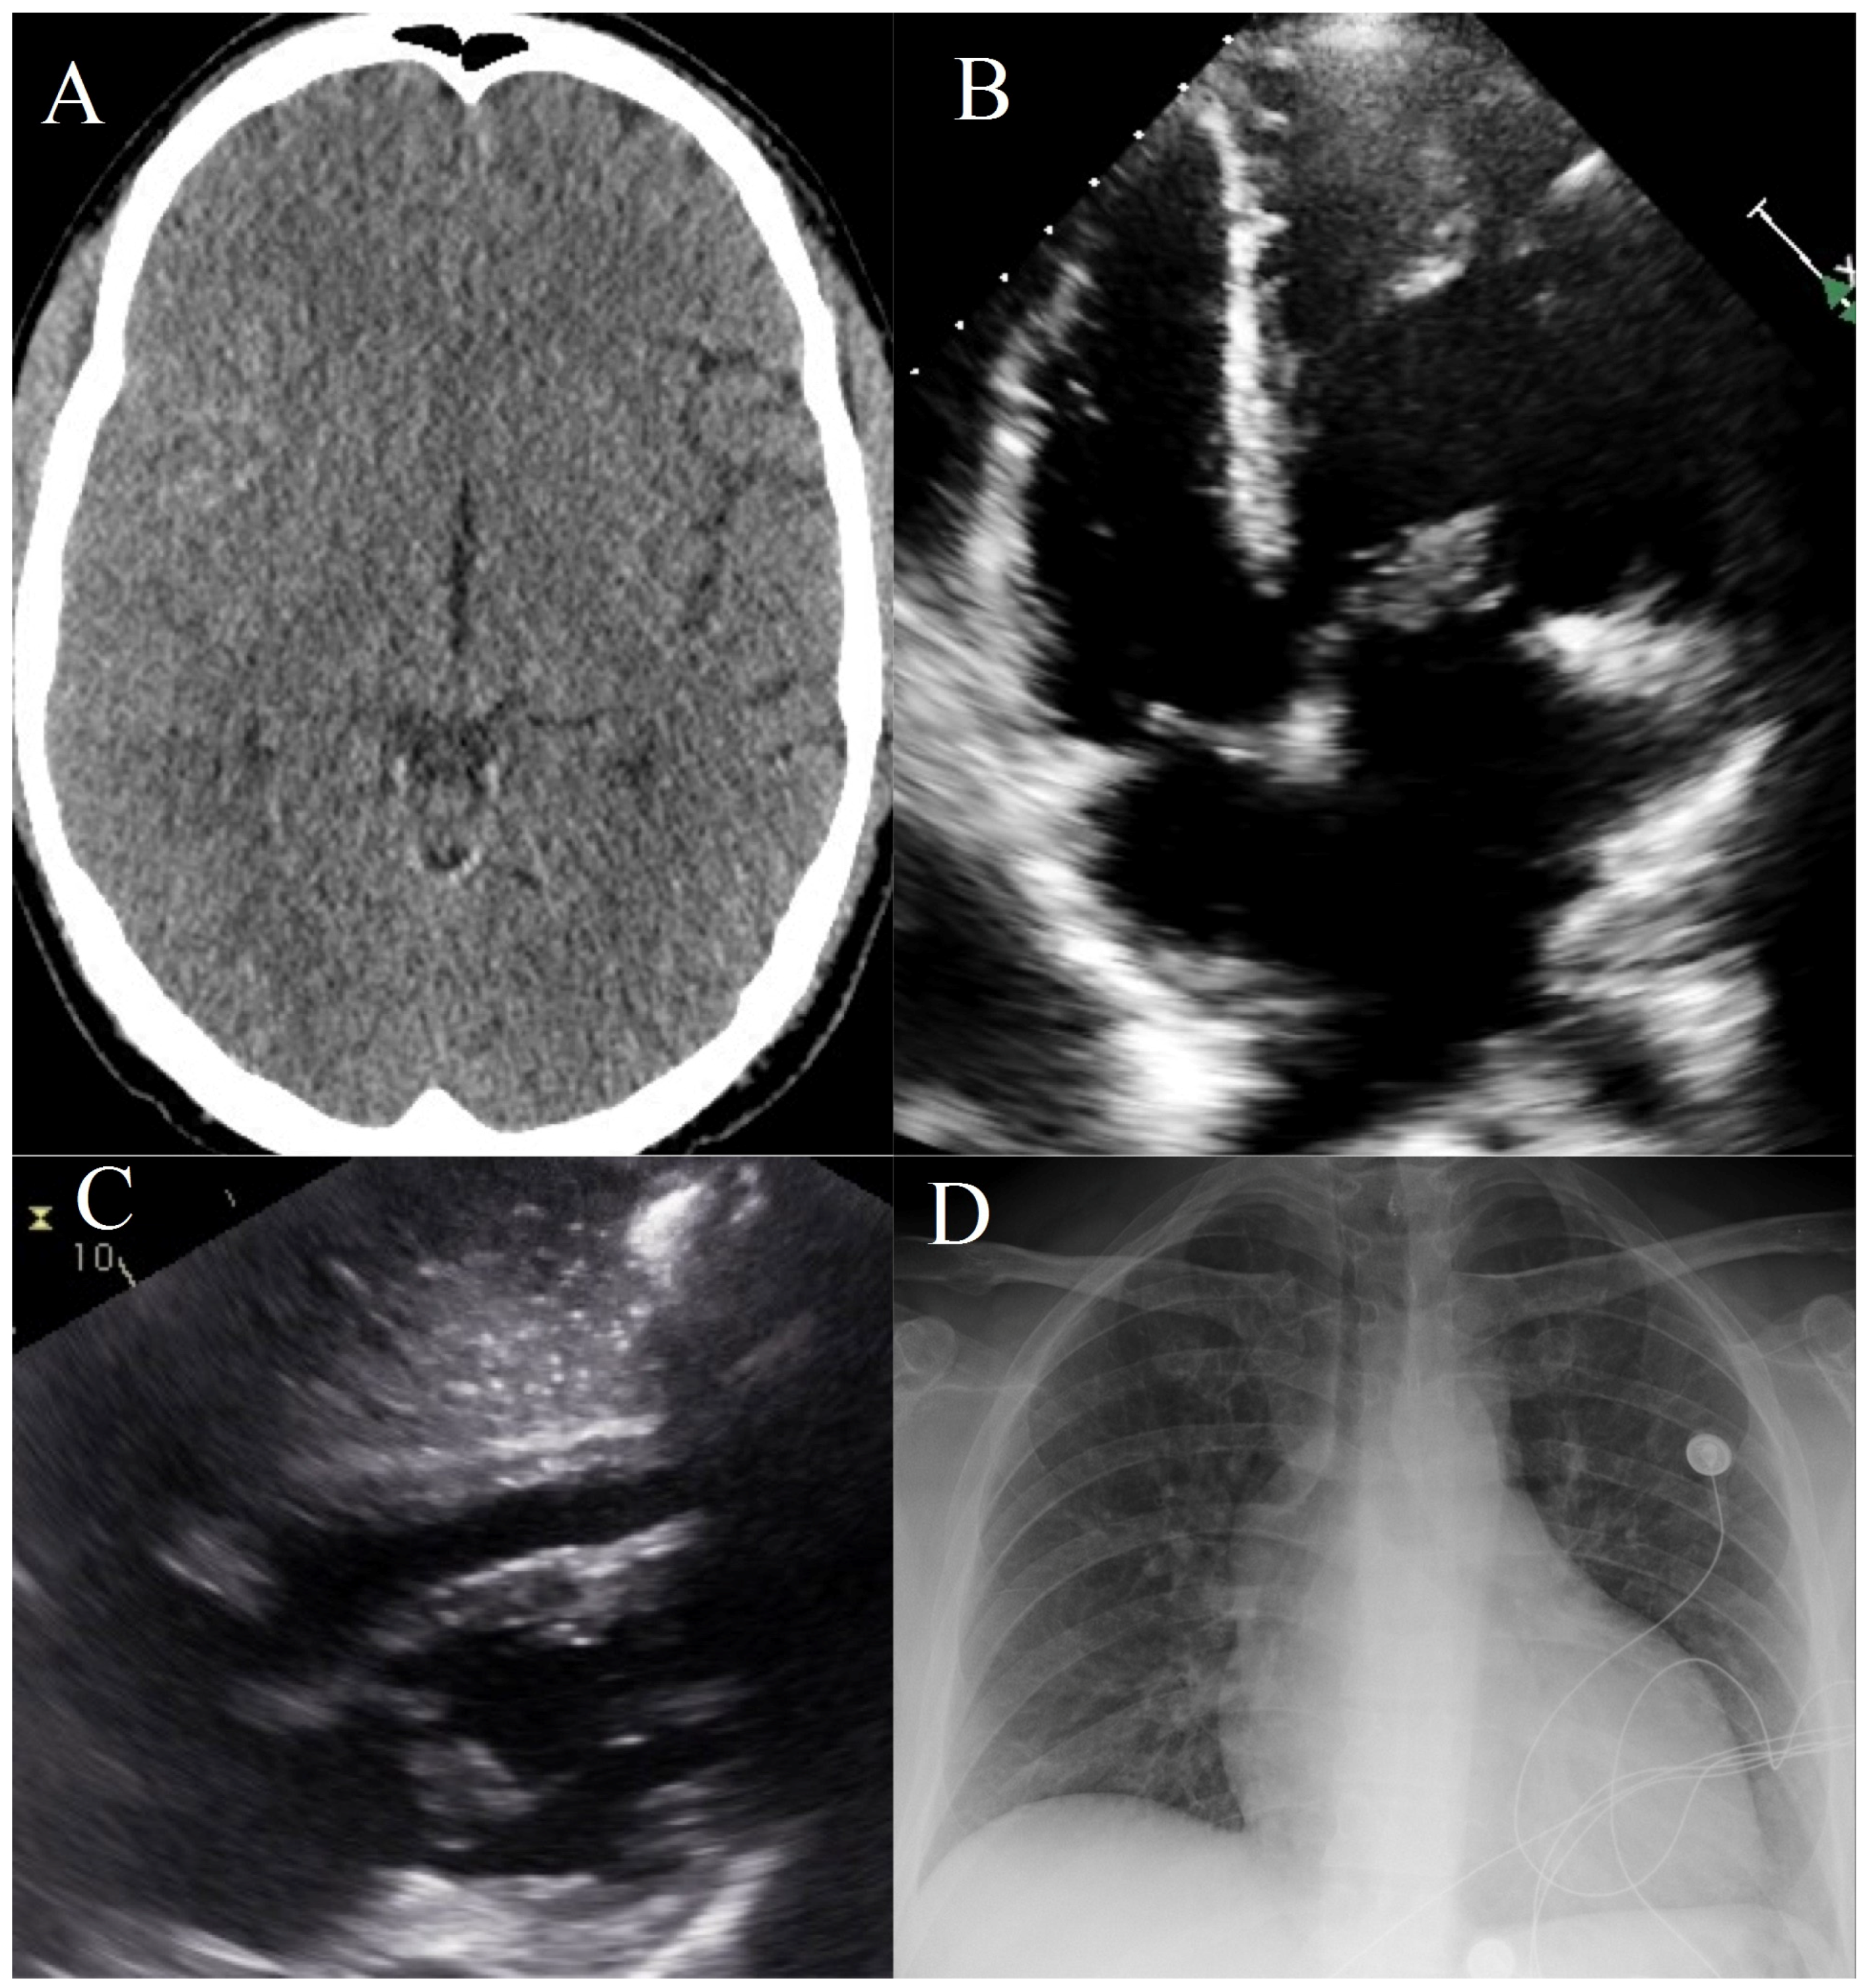

First Time Seizure in the Setting of a Congenital Heart Abnormality and MCA Mycotic Aneurysms

1. Clinical Presentation